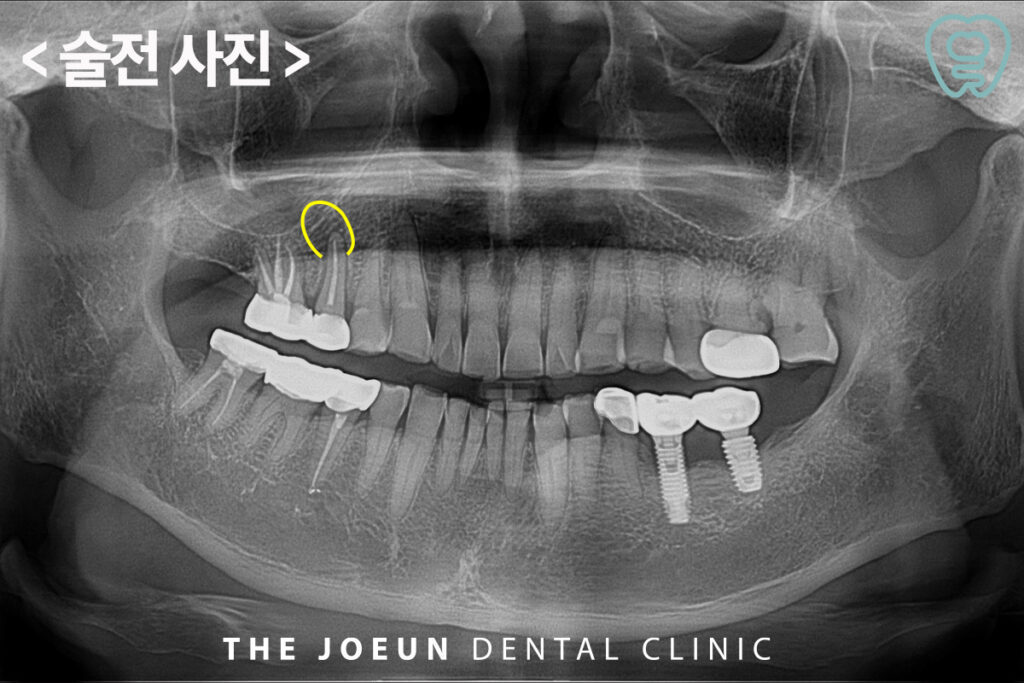

오늘은 뿌리 끝 염증이 있는 치아를 발치한 후 즉시 임플란트 식립을 진행하신 환자분을 소개해 드리도록 하겠습니다.

환자분께서는 오래 전 씌워두었던 오른쪽 위 어금니 부위가 조금 찝찝한 느낌이 드신다며 검진을 위해 내원해 주셨는데요. 외관상으로는 큰 문제가 없어 보였지만 두번째 작은 어금니의 뿌리 끝으로 커다란 염증이 관찰되고 있었습니다. 이미 신경치료 후 크라운이 되어 있는 치아로 발치 후 임플란트를 진행하기로 계획을 수립하였습니다.